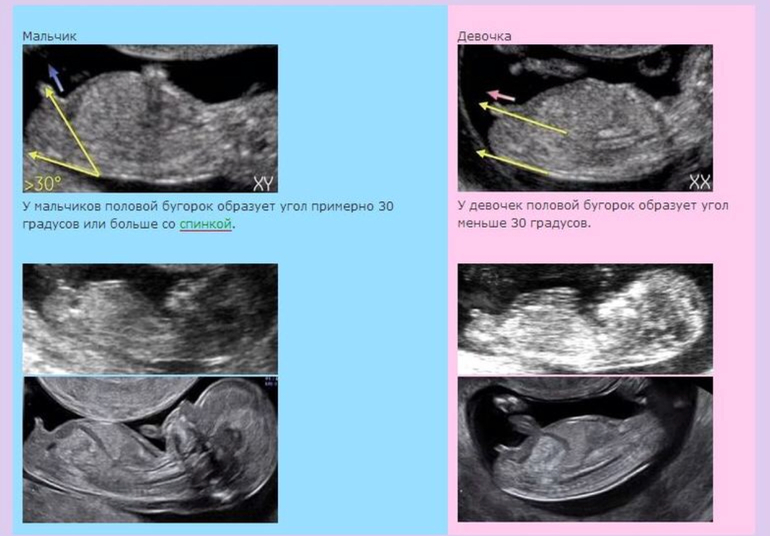

Девушки, доброе утро! Вчера был наш первый УЗИ-скрининг. Я так надеялась, что врач хоть что-то предположит, но она категорически сказала, что не понимает и на таком сроке ничего еще не видно. Но ведь у многих (читаю в интернете) на первом УЗИ предполагают пол. Может посмотрите и предположите кто там у меня в животике живет?